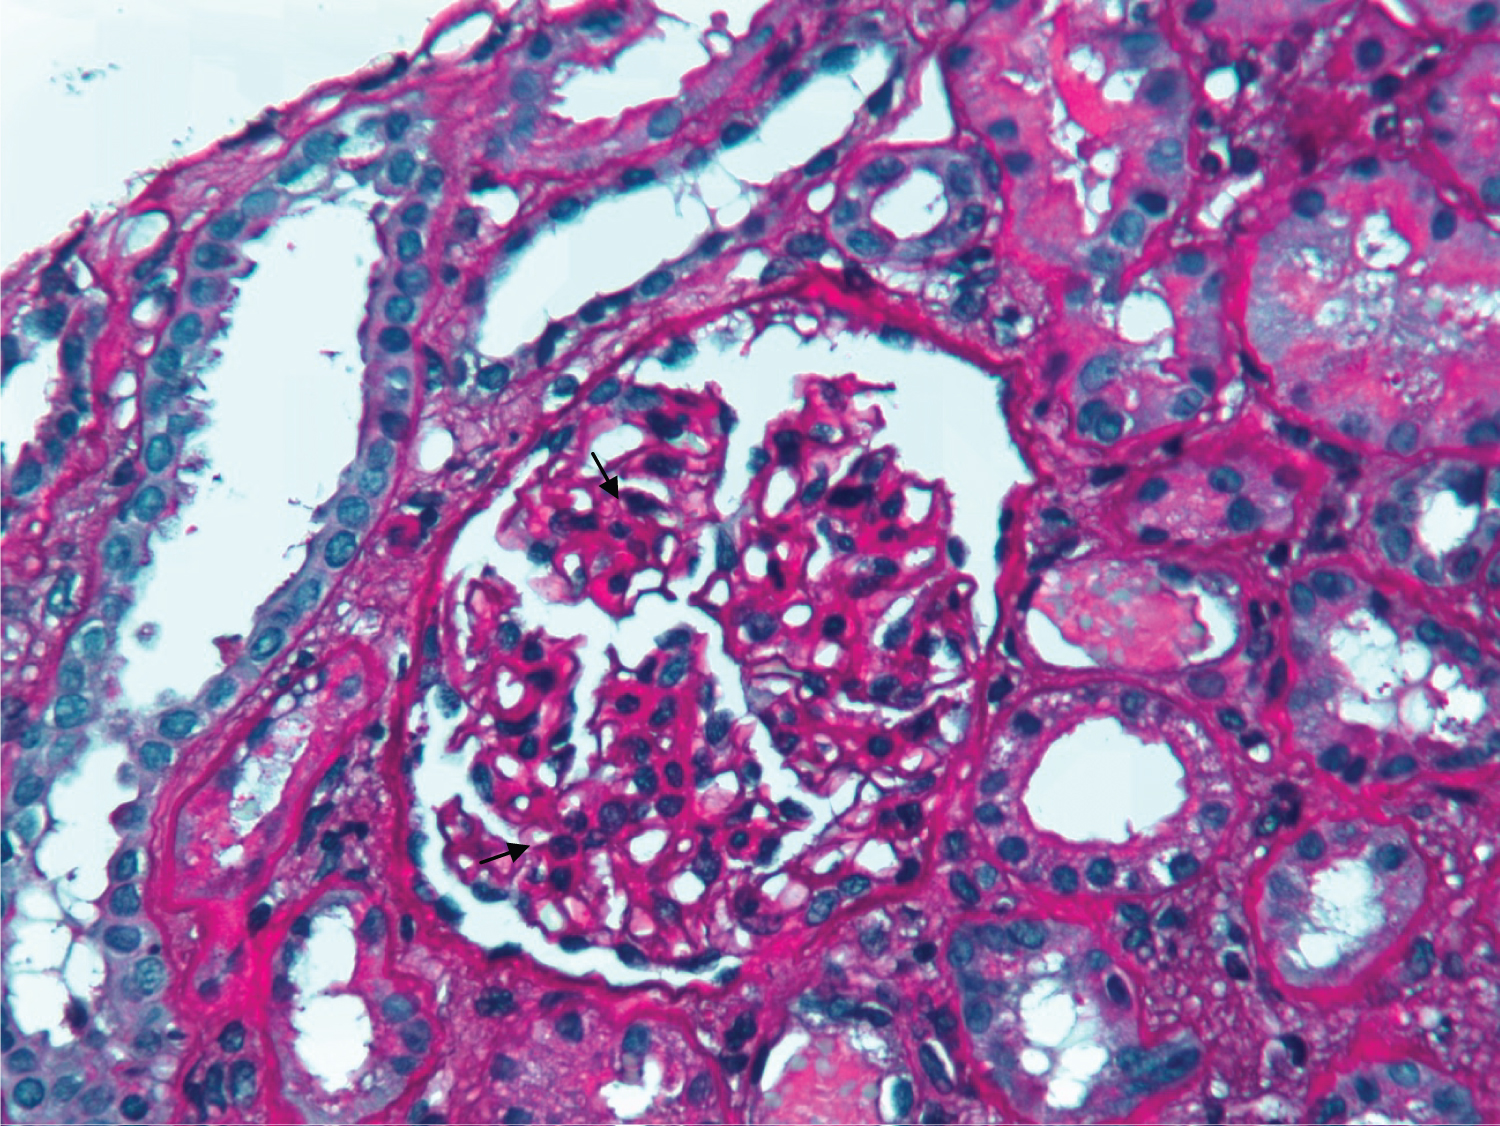

He was admitted for progressive anorexia, malaise and peripheral edema with one month of evolution. His vital signs were normal and besides bilateral peripheral edema, physical examination was unremarkable. Complementary tests revealed anemia (hemoglobin 10.7 g/dL) and acute kidney injury (AKI) (sCr 2.4 mg/dL) and the patient was transferred to the Nephrology Department for pursuing study. Additional study showed elevated erythrocyte sedimentation rate (102 mm/hour) and serum immunoglobulin (Ig) A (6,06 g/L; RV < 4.00); serum circulating immunocomplexes (89.31 RU/mL; RV < 20); mixed alkalosis and hypokalemia on arterial blood gas (pH 7.503, pCO2 26.2 mmHg, HCO3 22.9 mmHg, K 3.2 mEq/dL); urinary protein-to-creatinine ratio of 237 mg/g, urine specific gravity of 1,008 and leukoerythrocyturia on urinalysis (377/uL and 106/uL, respectively). Urinary sediment showed abundant dysmorphic erythrocytes (RBCs) and RBC casts under microscopy, with lipiduria and renal tubular epithelial cells (Figure 1). Further study, including monoclonal, polyclonal and infectious panel, was negative. Renal ultrasound excluded urinary calculi or obstruction. A kidney biopsy was performed. Under light microscopy, glomeruli revealed slight mesangial expansion and proliferation (Figure 2). The interstitial compartment showed mild mononuclear interstitial inflammatory infiltrate and fibrosis involving about 30% of the biopsy fragment (Figure 3). There was also acute tubular necrosis foci and tubular hematuria. No interstitial granulomas or crystal clefts were found. Congo red staining for amyloid was negative. Direct immunofluorescence examination of frozen renal tissue demonstrated mesangial deposits positive for IgA (++) and C3 (++) (Figure 4). These findings were consistent with interstitial nephritis due to salicylates and IgA nephropathy secondary to UC.

Figure 2: PAS x 400 - Slight mesangial expansion and proliferation on glomeruli (black arrows) and acute tubular necrosis foci (white arrow). View Figure 2